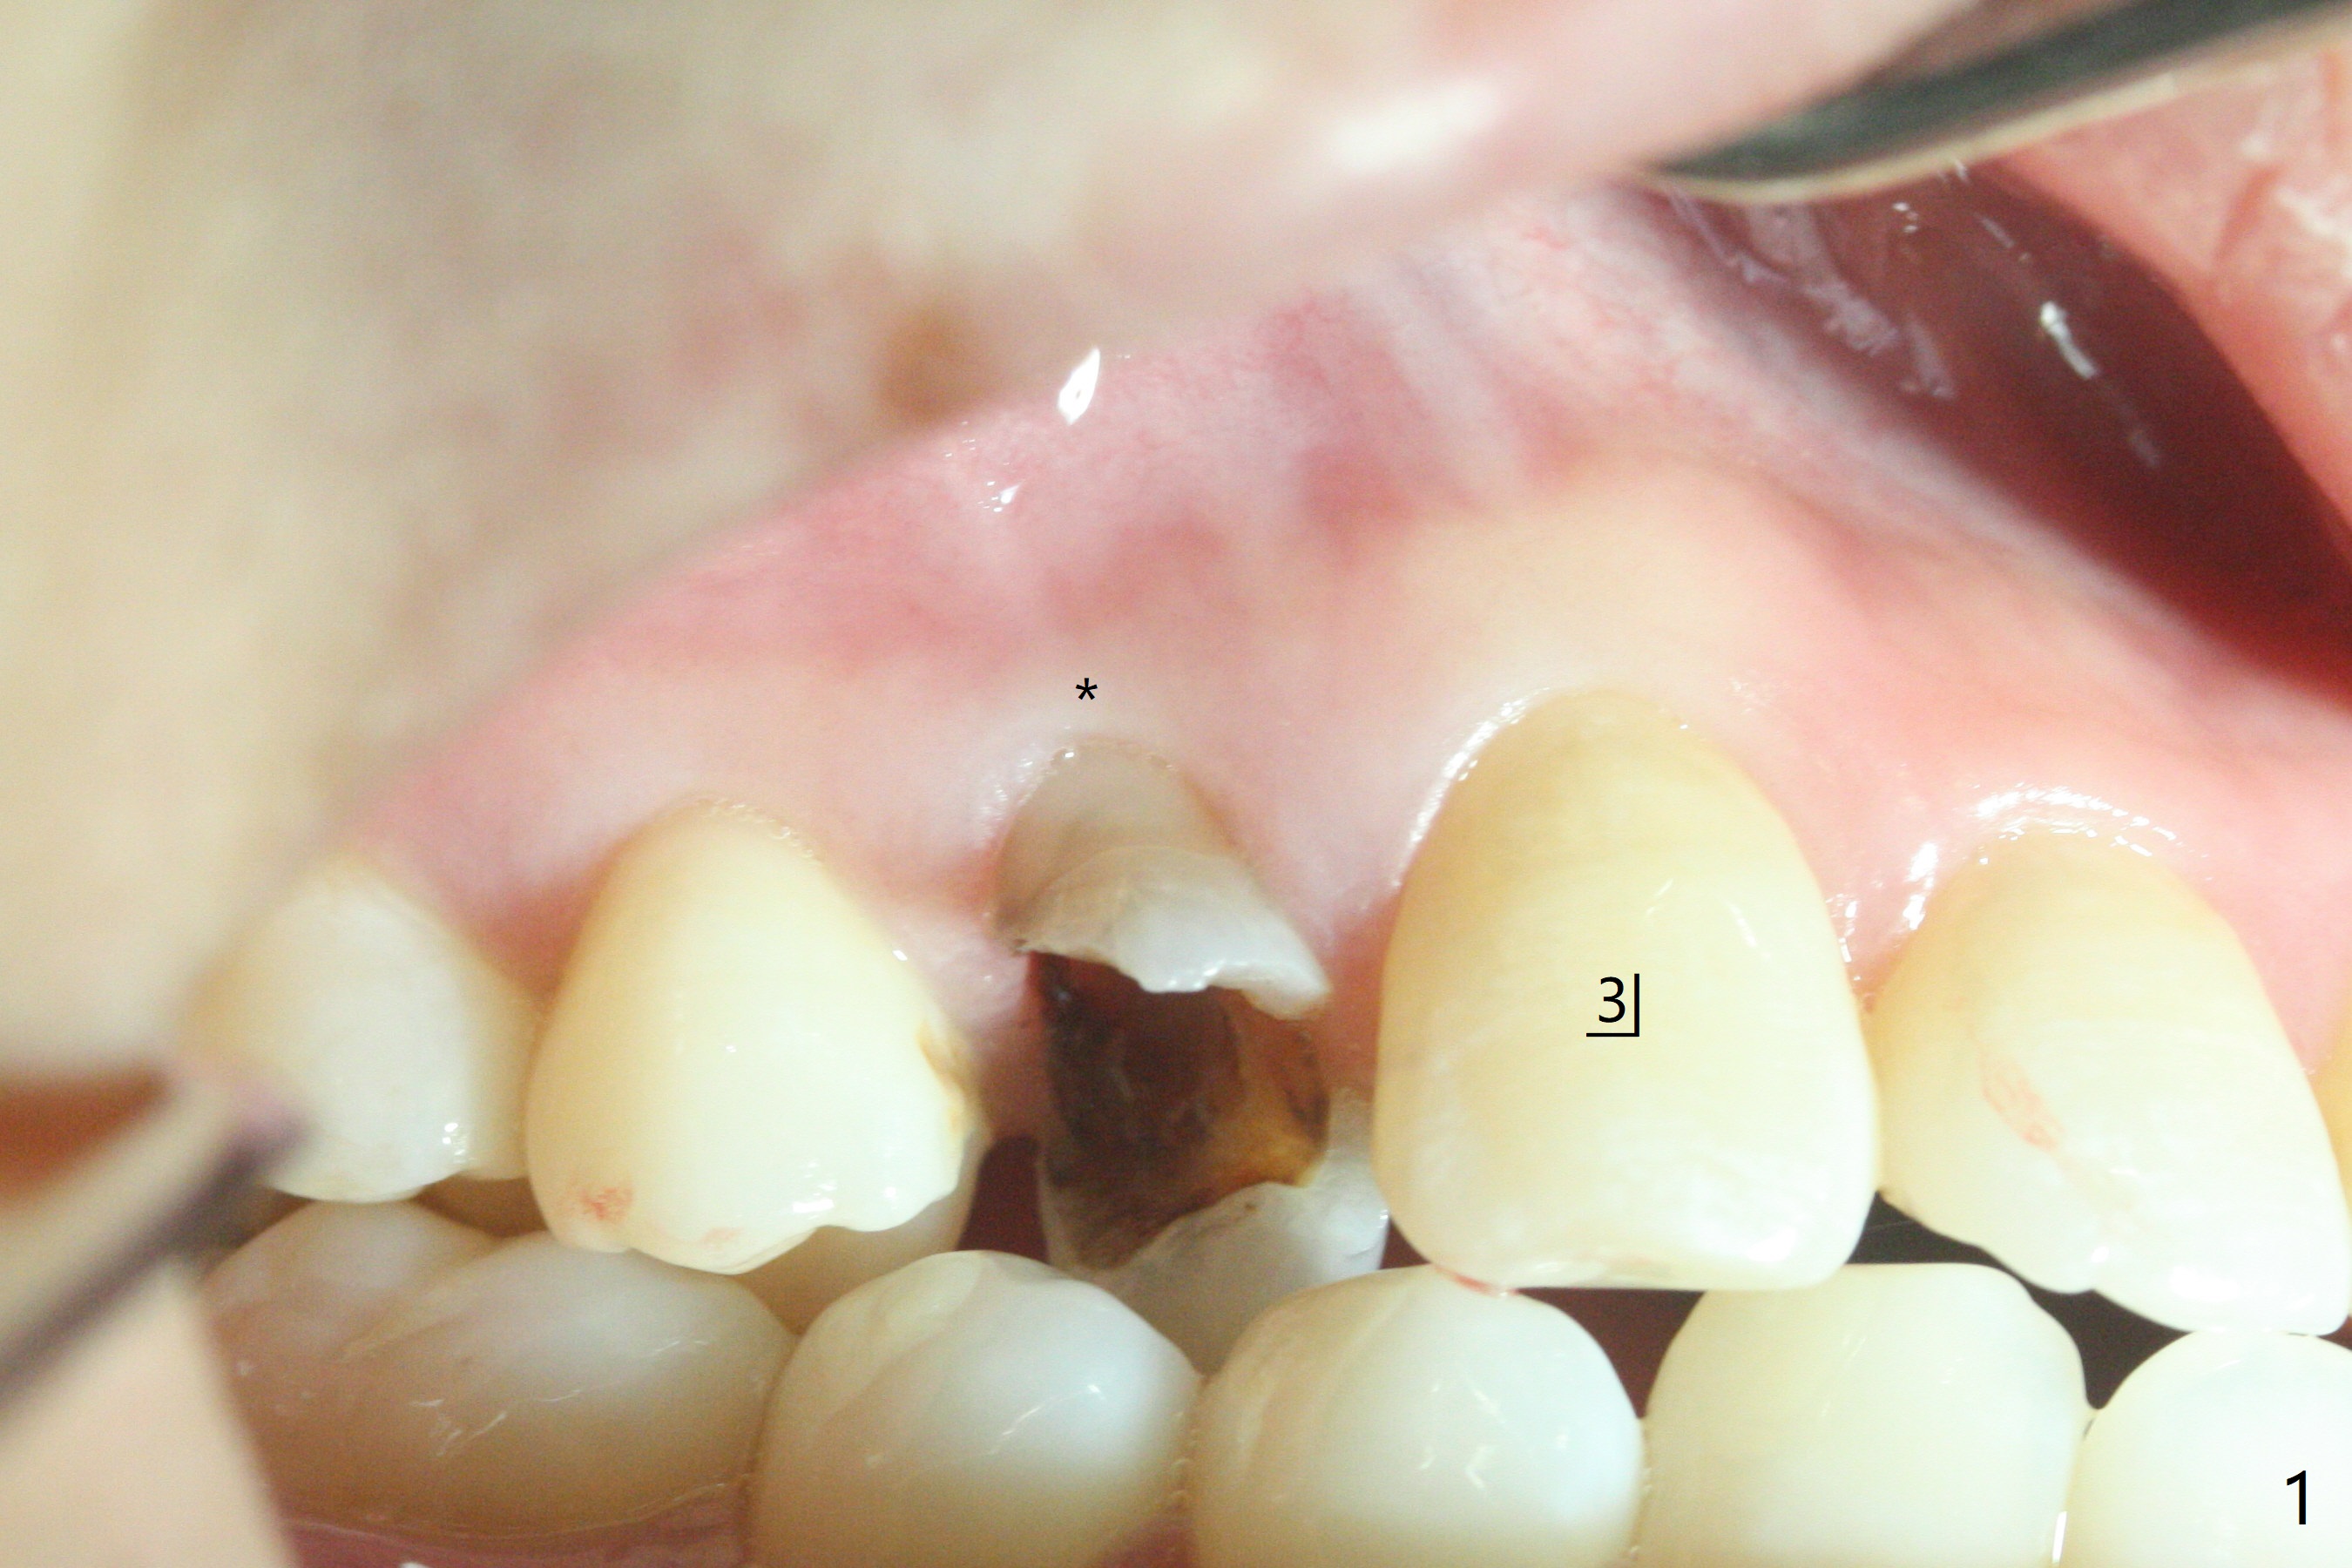

今天临床实践让我对植骨概念和操作有两方面突破,与大家分享讨论。PRF/sticky bone(粘性骨粉)以及血小板因子(成品)对软硬组织缺损修复重建无疑起到不可缺少作用。但是大多数拔牙病例并不是那么严重,放置骨粉和覆盖胶原膜足够了。为了避免费时的缝线固定胶原膜,介绍一种简易固定方法,助手可以做。31岁女不想保留严重龋坏右上4(图一至四,拍摄临床照片,与后期比较,但愿简易植骨不产生骨板塌陷),虽然术前根尖片显示根尖阴影(图四),术中没有根尖骨板缺失。估计没有严重骨板缺损,她又年轻,再生能力强,所以做简易植骨(异体骨,图五),也就是不需要PRF或者血小板因子,骨粉表面放置GEM CAP(9-12月吸收膜),由胶水固定(图六),在放置牙周敷料前,在胶原膜表面涂一层含有抗单纯疱疹病毒凡士林(图七),但愿敷料脱落时,不至于把胶原膜带下来。术后第六天,病人由于左上第二磨牙不适回来,说敷料脱落,没有不适,要求检查,其实膜也丢失(图八,九),骨粉好像挺稳定,没有做如何处理,尽管少量骨粉离开牙槽窝(<)。